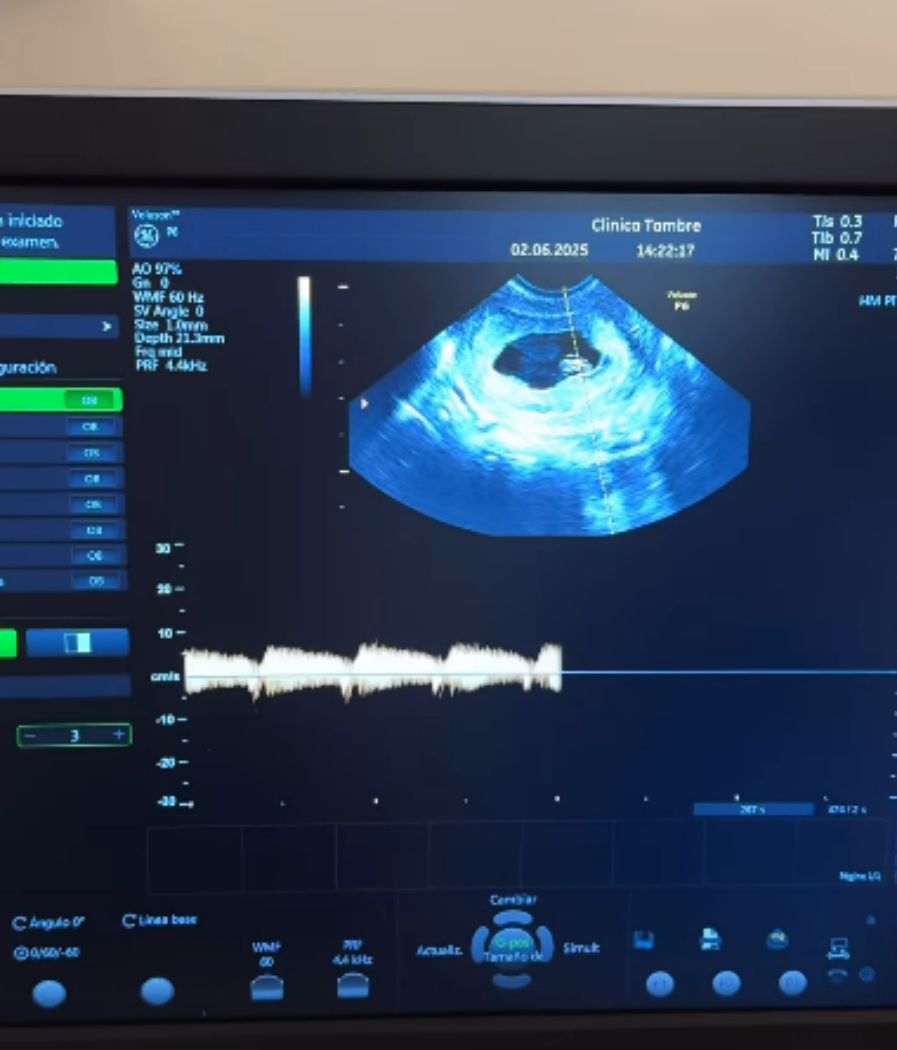

La influencer ha compartido en sus stories un vídeo en el que graba la pantalla del monitor en la que se representa el latido de su bebé y se le escucha decir: "Qué fuerte es, sí, mucho, genial"; unas palabras que confirma Tony Spina, que le da la razón en que su hijo está creciendo muy bien. En el story ha escrito: "Quiero llorar. Hoy hemos vuelto a la clínica y ha triplicado las medidas y el latido es perfecto".